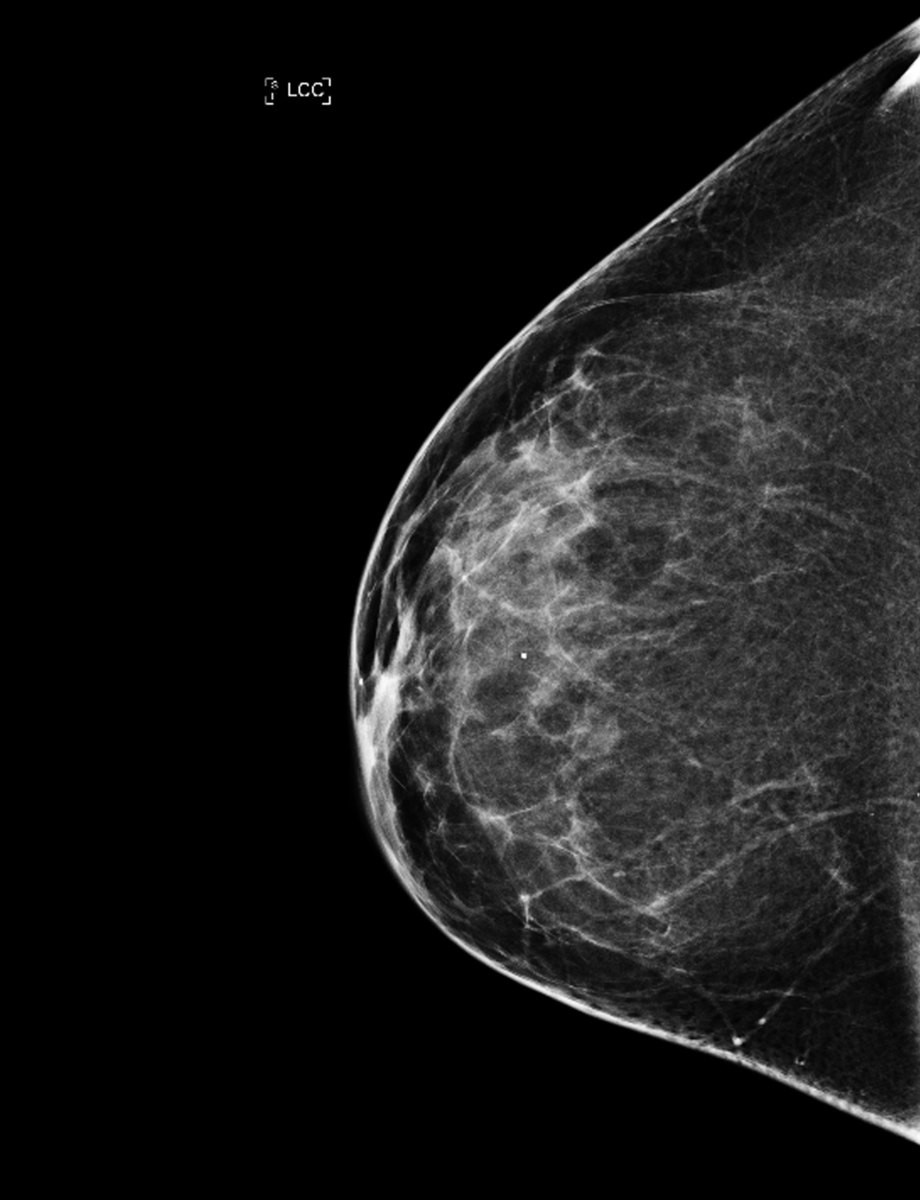

Vigdis skriver: «En gang i året gikk jeg til Volvat og fikk tatt mammografi av brystene, og besøkene der var alltid forbundet med en ubehagelig form for spenning, etterfulgt av en befriende lettelse når jeg kunne gå derfra.»

Mammografiprogrammet hevder på sin side at ulike internasjonale samlestudier viser 30 prosent dødelighetsreduksjon blant de som møter til mammografiscreening , men også at forskjellige resultat skyldes ulike metoder og data. Ifølge en studie fra Mammografiprogrammet kan KI-algoritmer som allerede finnes på markedet, brukes til å utvikle mer persontilpassede screeningprogrammer og identifisere personer i risikosonen mye tidligere . Det er fortsatt mye å finne ut av før det kan settes inn i ordinær drift. Ifølge ny nasjonal kreftstrategi, som ble lansert i februar, skal screening for både prostata- og lungekreft vurderes av Helsedirektoratet.